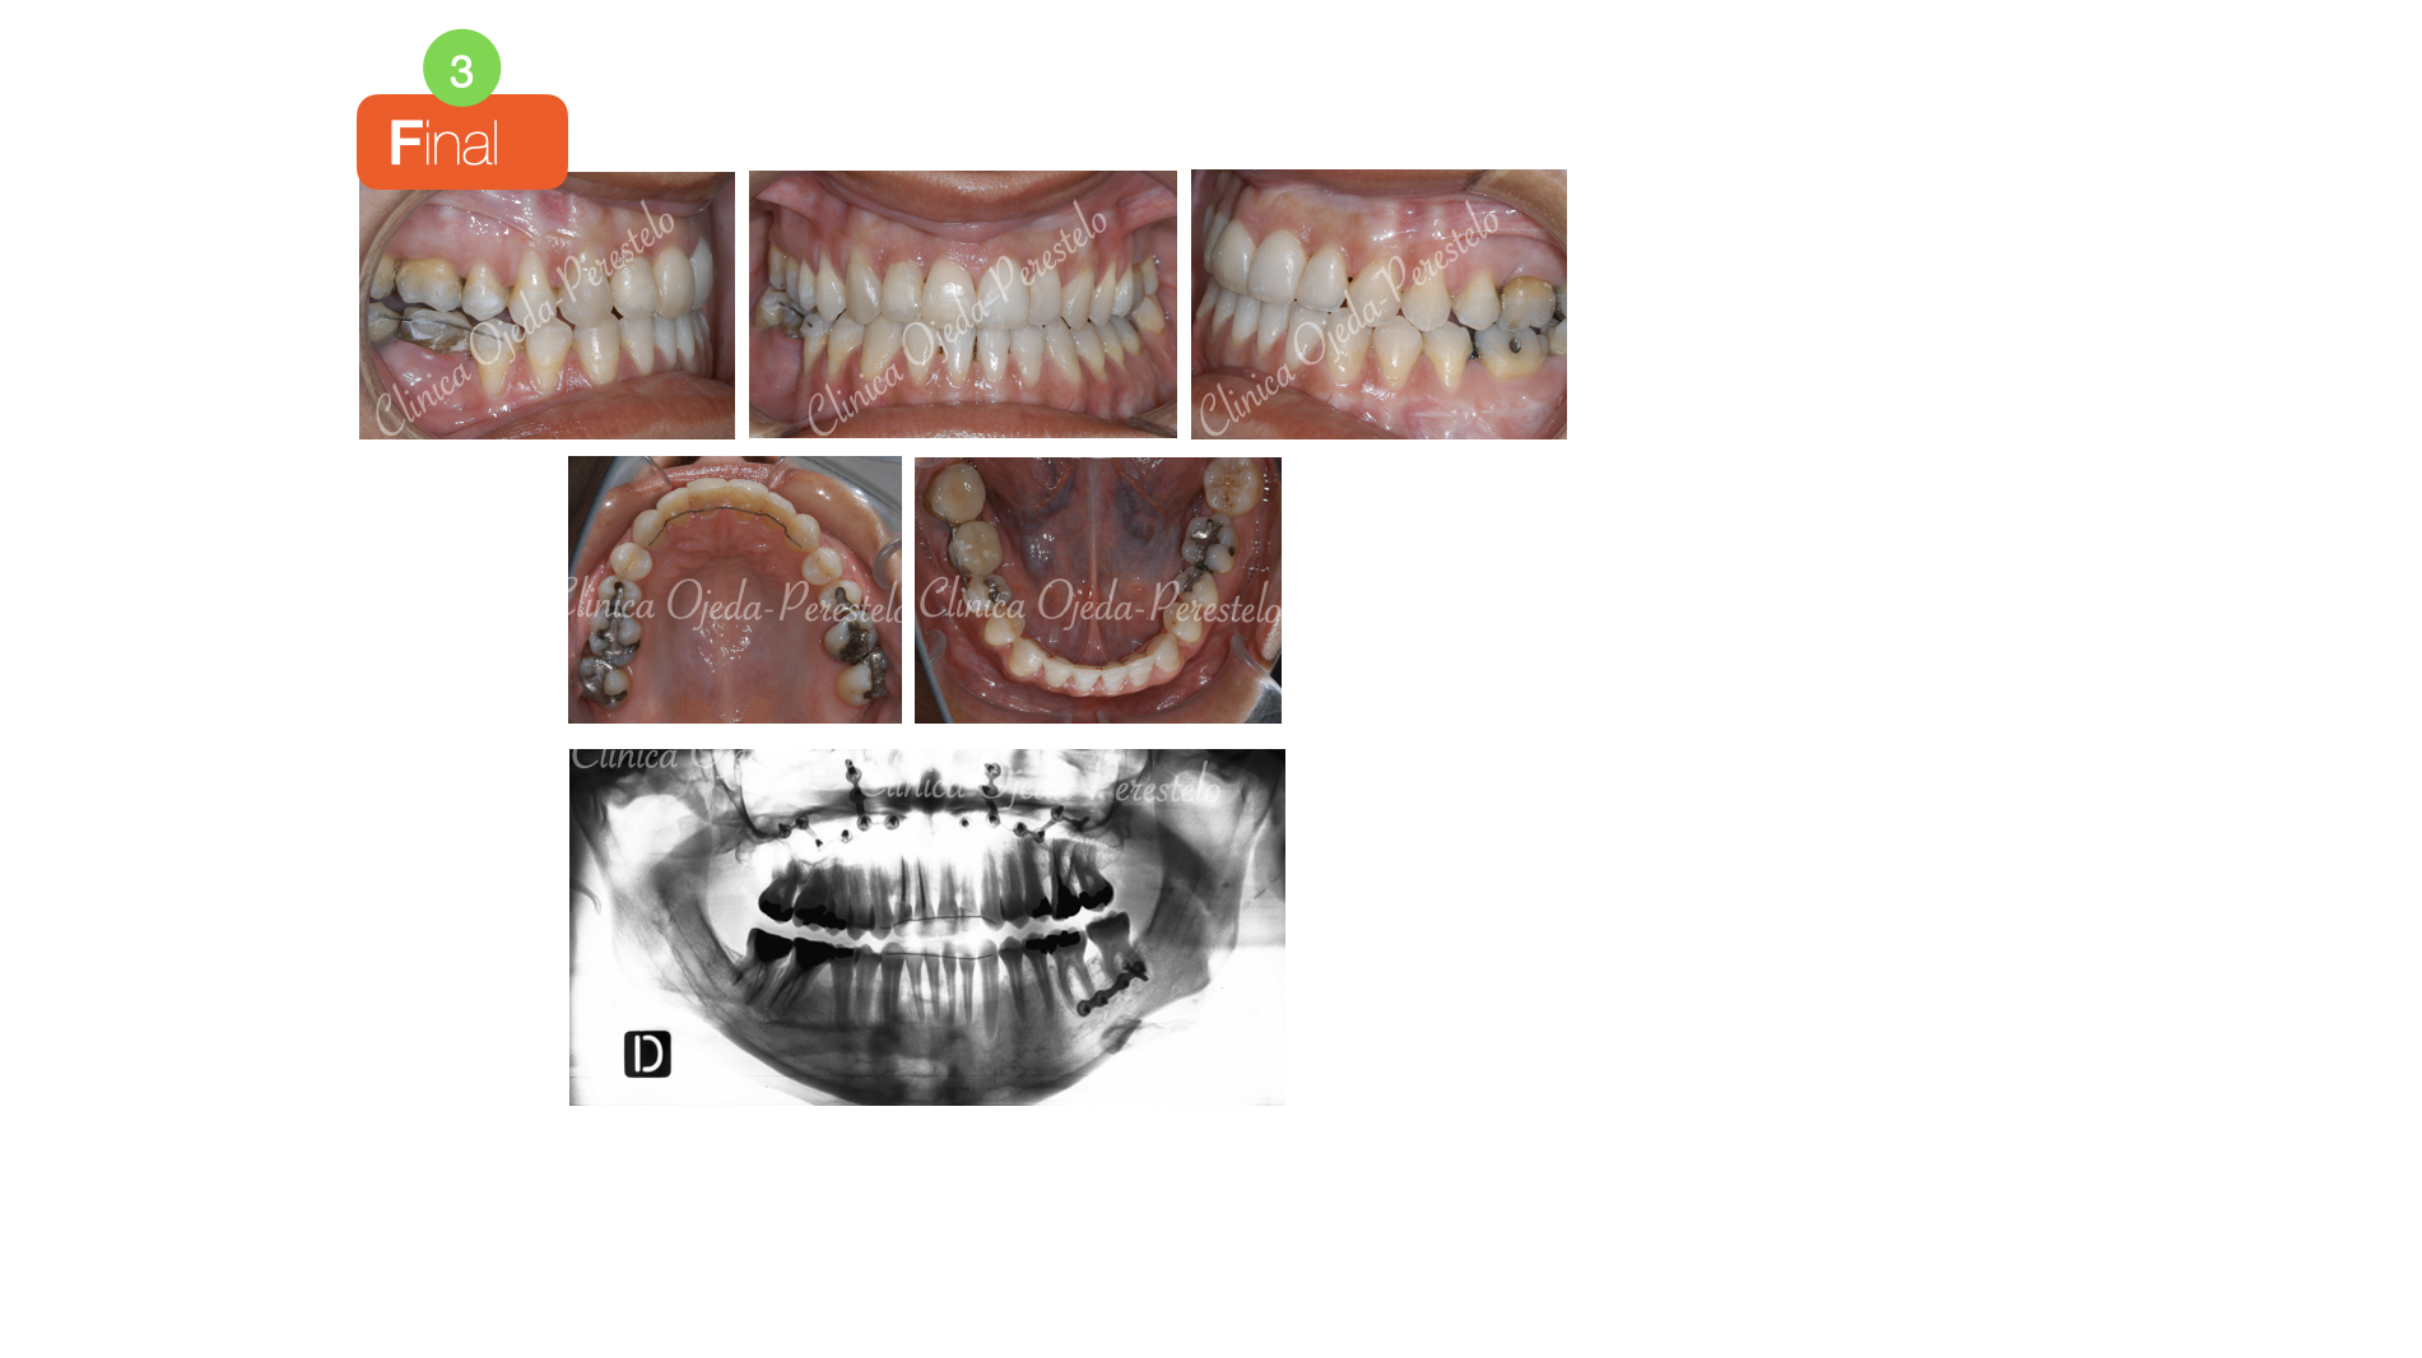

La intervención quirúrgica ha sido realizada por el equipo del Dr Hdez-Alfaro y se planificó con Lefort y Avance del Maxilar conjuntamente con Osteotomia Sagital de Rama para centrado y retrusión Mandibular unilateral hacia la izquierda. Quisiéramos destacar la mejoría en el perfil, su sonrisa y en su articulación dentaria tras finalizar el tratamiento. Presentamos la estabilidad del caso 20 años después.